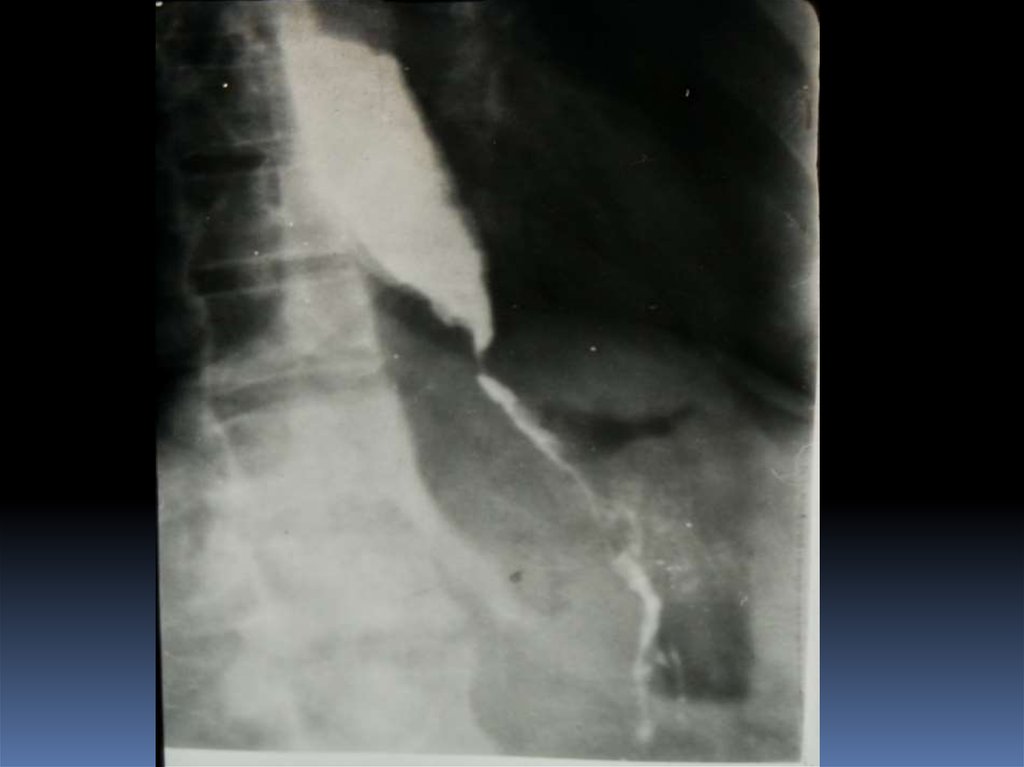

16. Рентгенодиагностика рака желудочно-кишечного тракта

Рентгенодиагностика

рака желудочнокишечного тракта

17. Классификация рака органов ЖКТ

1. Экзофитная форма:

2. Эндофитная форма:

узловая форма;

диффузноинфильтративная

форма;

полипоподобная

чашеподобная форма. инфильтративноязвенная.

3. СМЕШАННАЯ ФОРМА – 10-15%